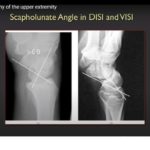

Essential Radiography of the Upper Extremity

Courtesy: Christopher Beaulieu, Professor of Radiology, Stanford University, USA